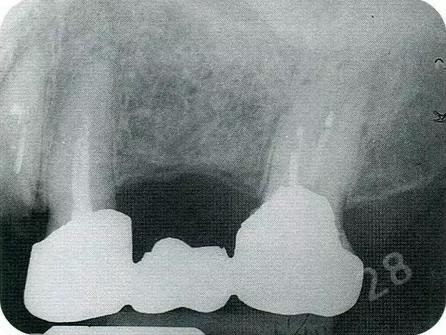

▼圖16-1 ▼圖16-2

圖16-1 對(duì)右上6.7分叉部病變處理時(shí),對(duì)包括右上4.5進(jìn)行齦瓣分割,確認(rèn)骨缺失狀態(tài)。右上7頰側(cè)存在著12mm的骨緣下缺失。

圖16-2 右上6水平的分叉部病變到達(dá)了III度。